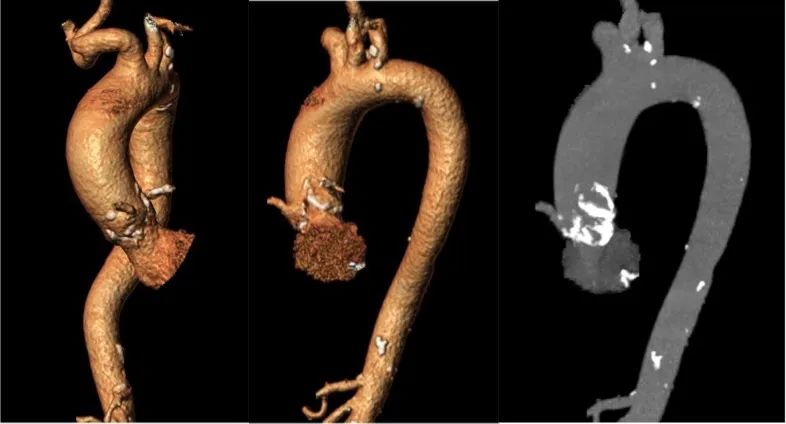

主动脉弓: